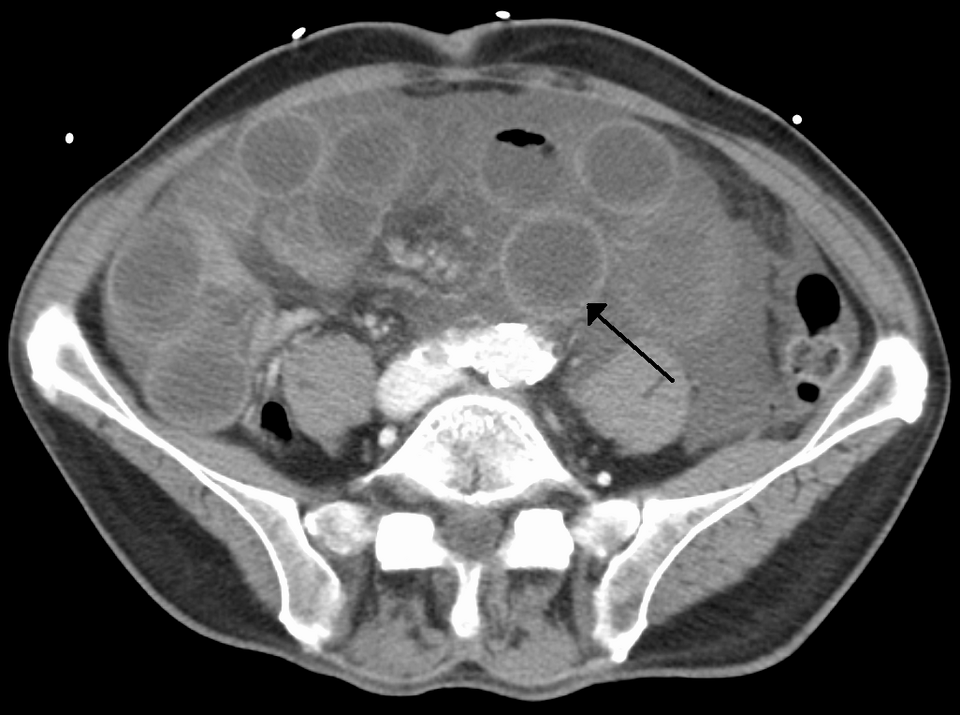

Mesenteric Artery Occlusion

Sudden blockage of intestinal arteries can turn a routine meal into a life-threatening crisis

The moment a mesenteric artery becomes occluded, the fate of the intestines hangs in the balance, teetering between survival and catastrophic injury. This blockage cuts off the vital blood supply to the intestines, leading to...